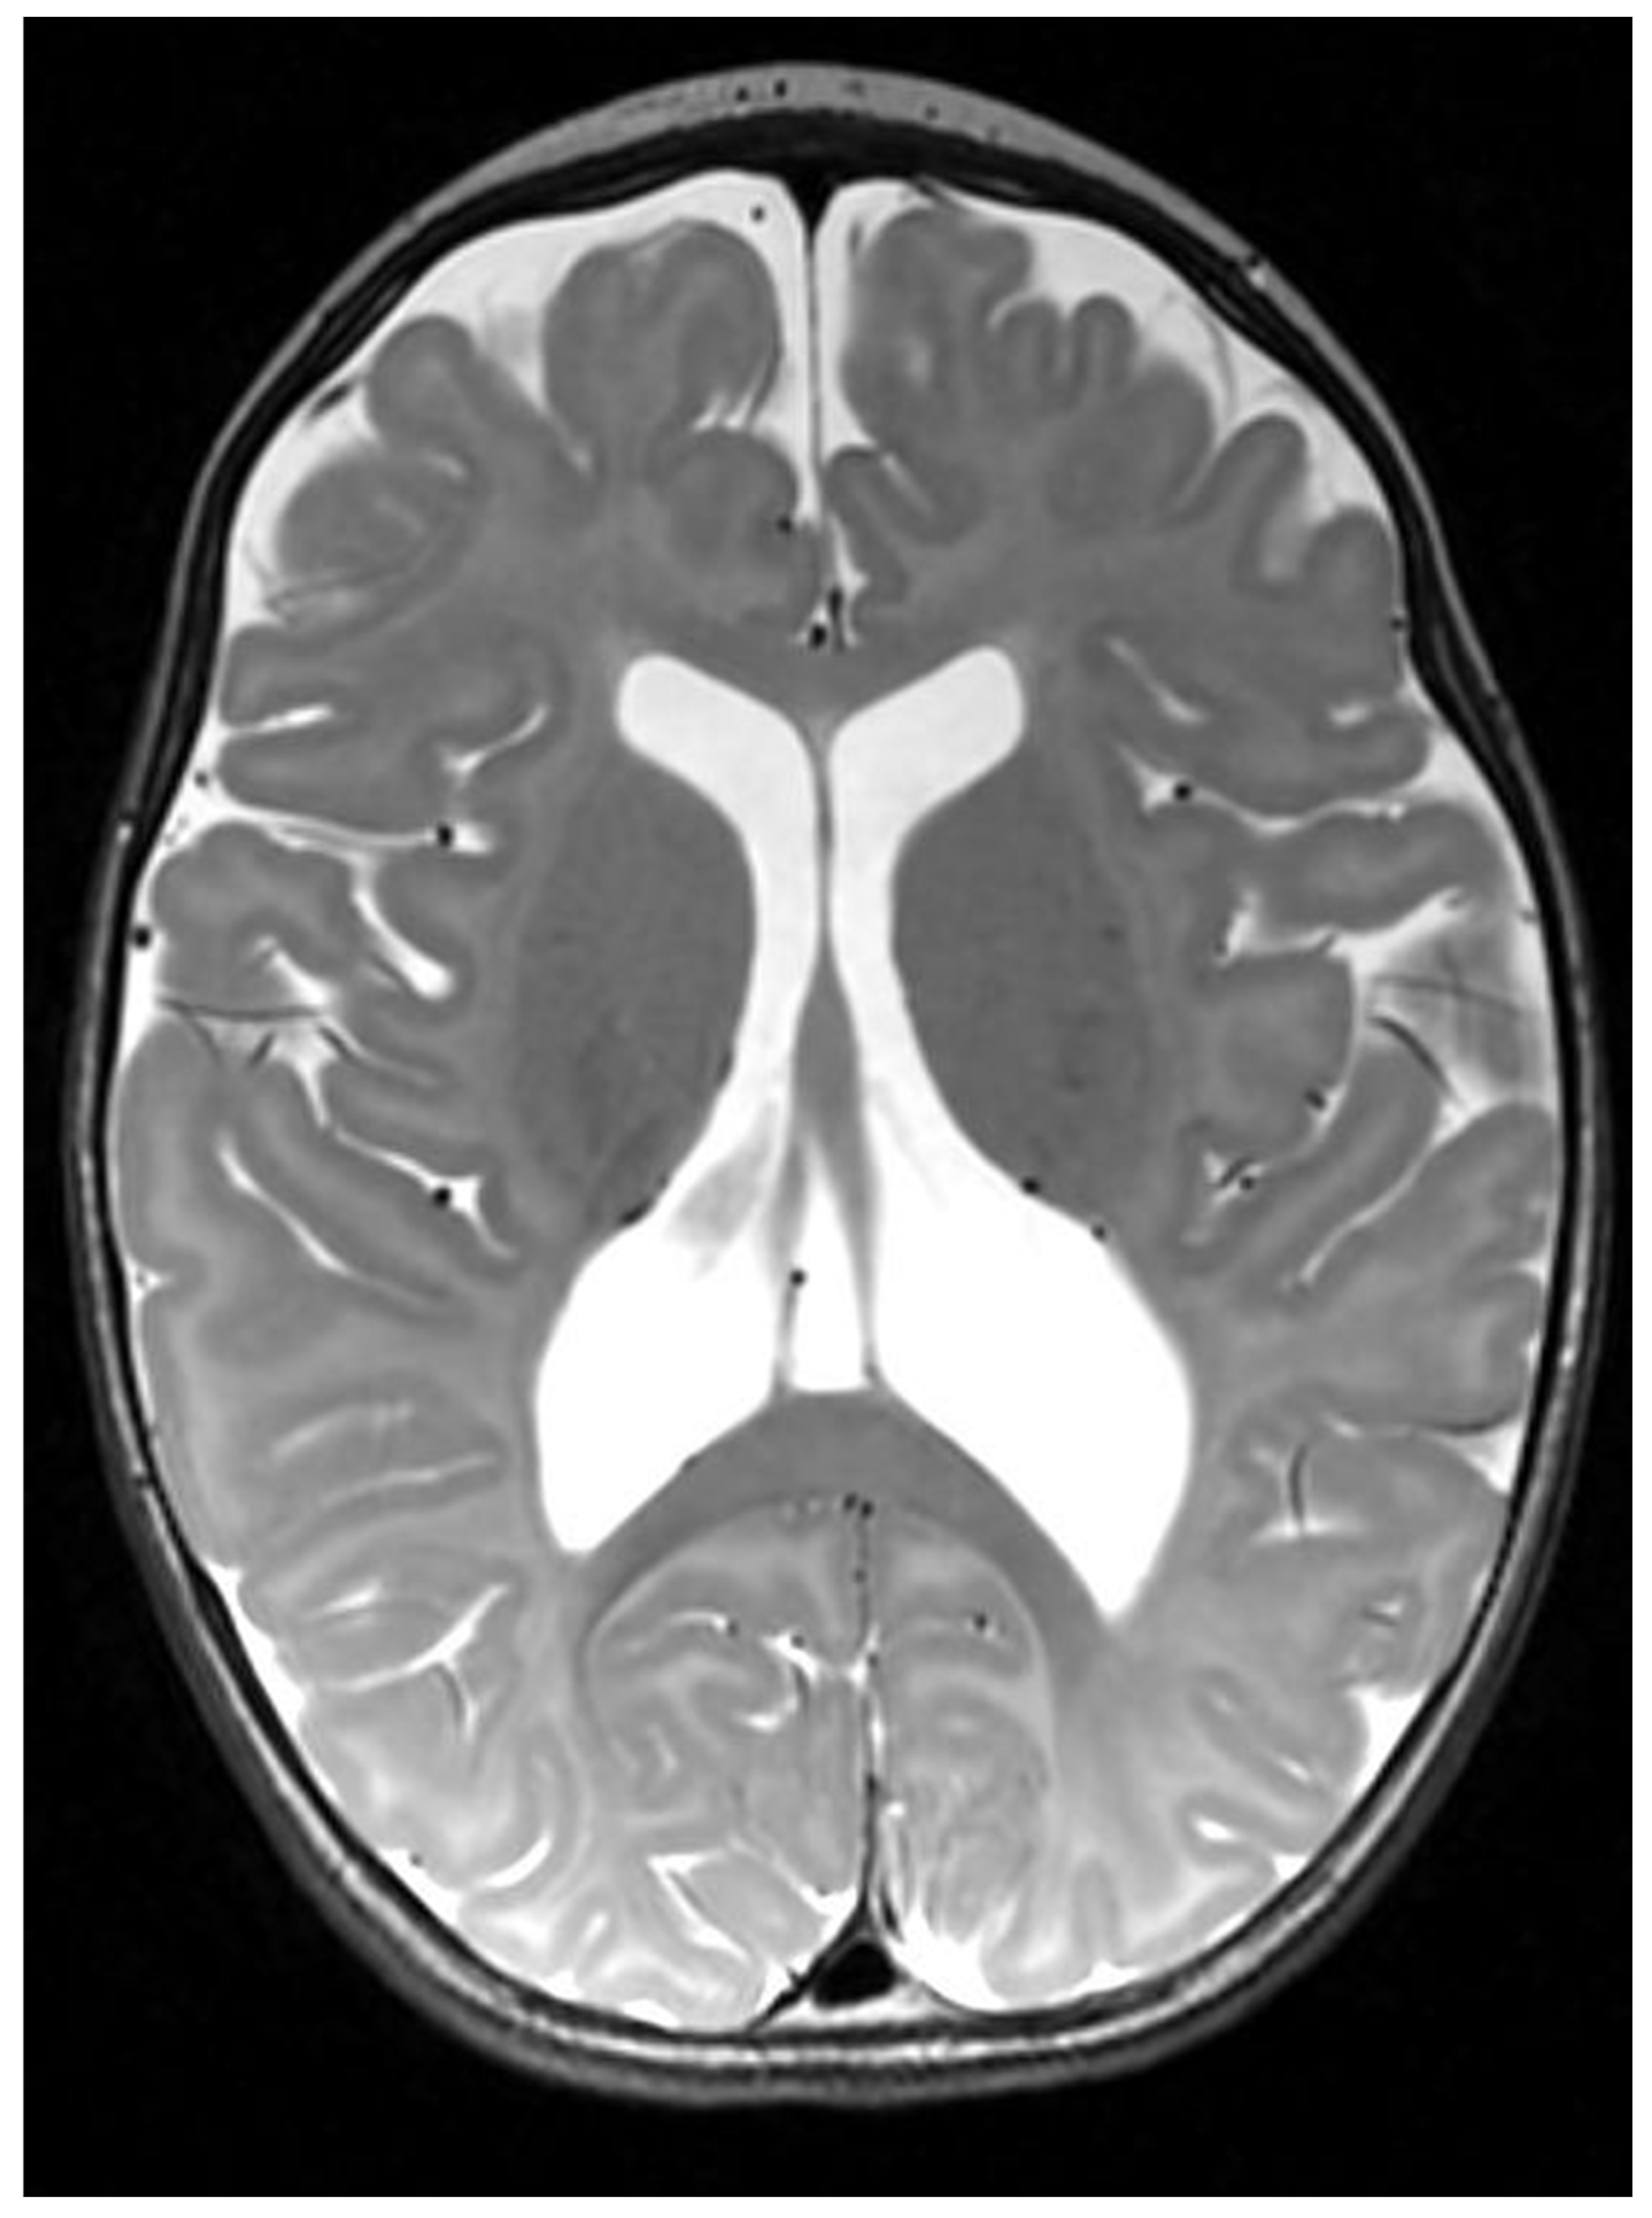

| MRI Findings | Supra-tentorial cortical atrophy with ventricular dilatation, bi-frontal white matter abnormalities, and delayed myelination | Enlarged lateral ventricles and formation of cysts in the cortex and white matter of the whole cerebral structures | Periventricular cystic changes | Cortical malformations including ventricular colpocephaly, polymicrogyria and possible subependymal heterotopia |